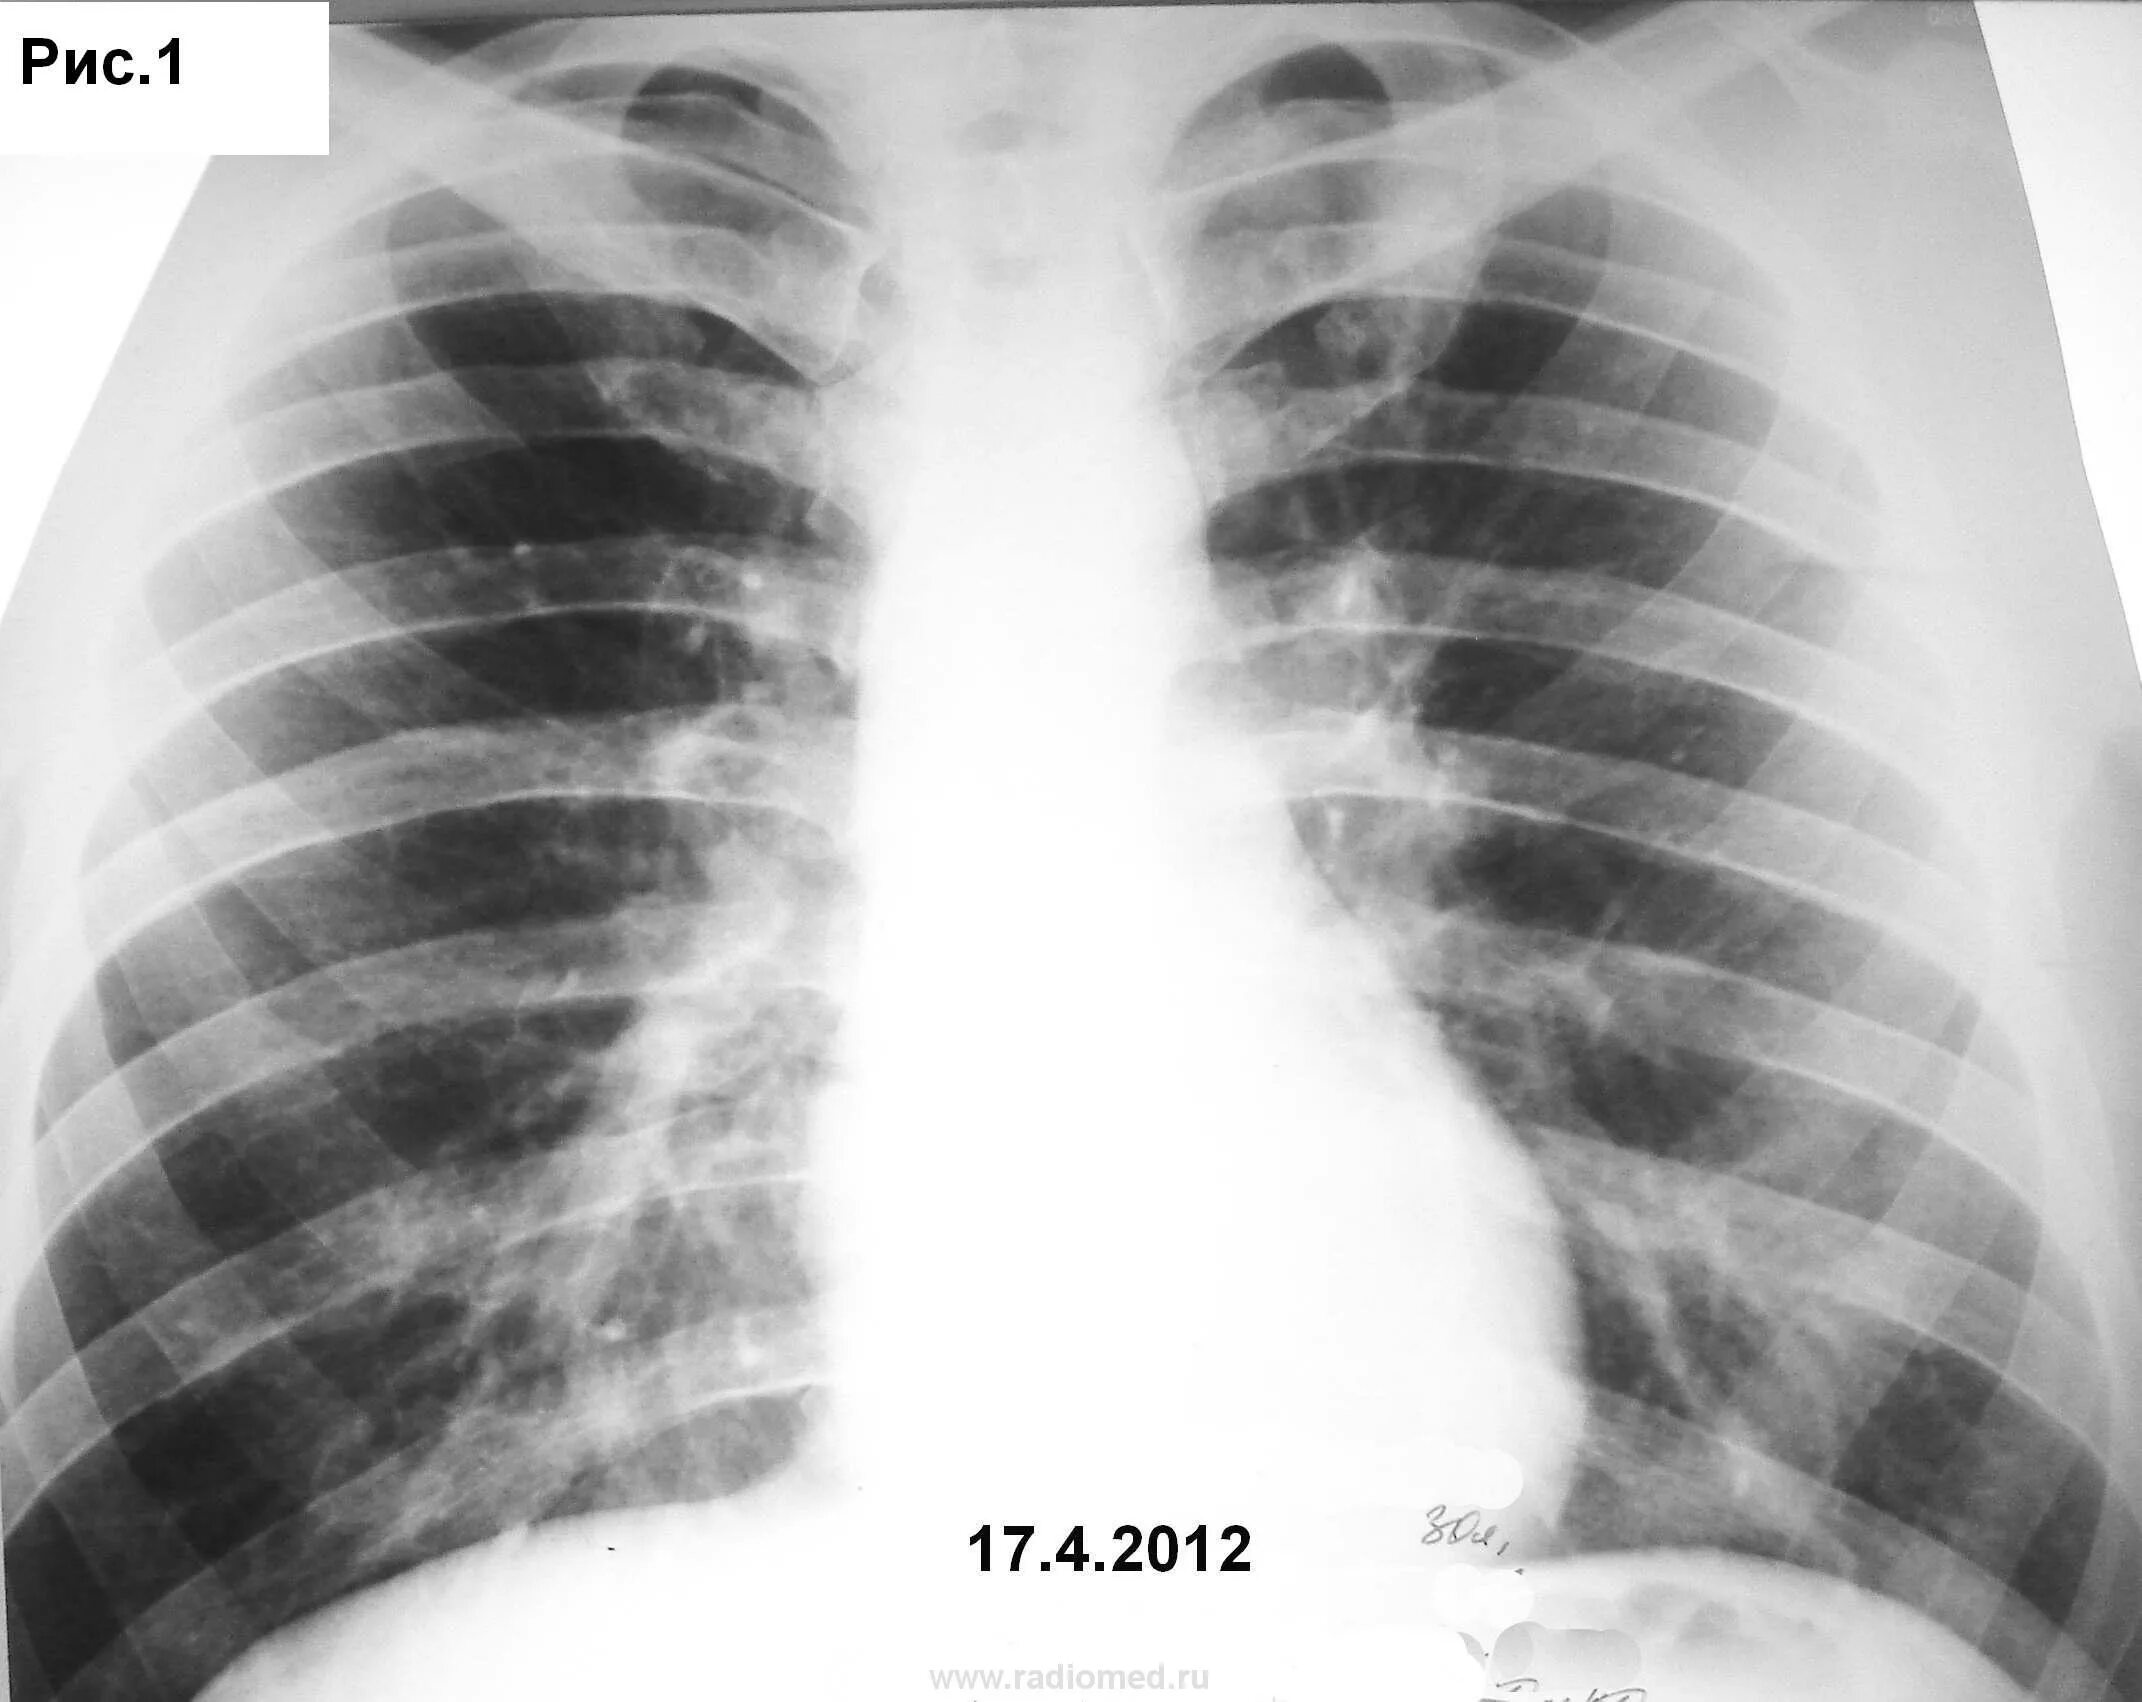

Флюорография в бутово